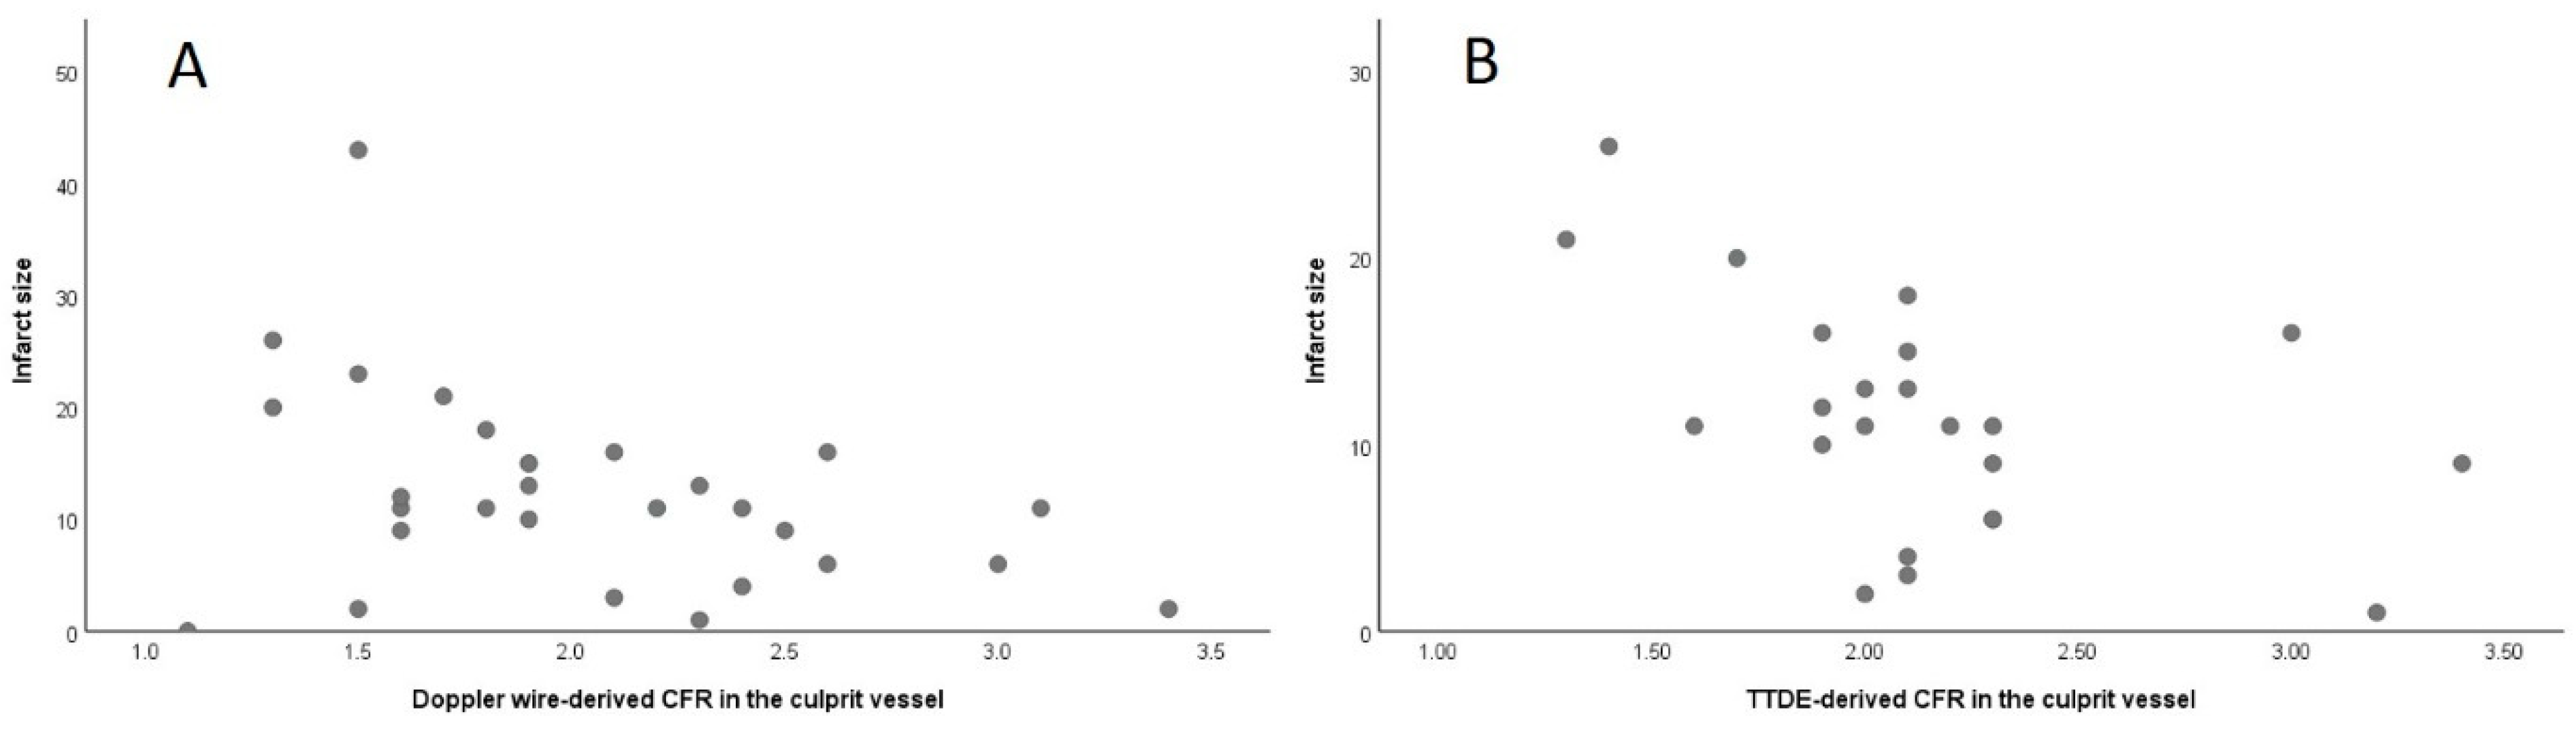

3.3. Association of Invasive and Non-Invasive CFR with Final Infarct Size

3.4. Association of Invasive and Non-Invasive CFR with LV Function

4.2. Echocardiography-Derived CFR Predicts Infarct Size and LV Function after STEMI